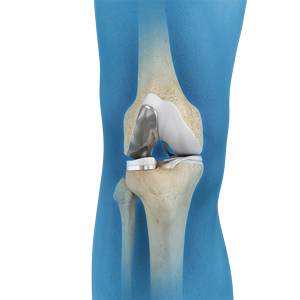

Total Knee Replacement

What is Total Knee Replacement? Total knee replacement, also called total knee arthroplasty, is a surgical procedure in which the worn out …

What is Total Knee Replacement? A total knee replacement surgery involves replacing the damaged surfaces of the articulating bones with artificial implants. …

Anatomy of the Knee The knee is made up of the femur (thighbone), the tibia (shinbone), and patella (kneecap). The meniscus, the …